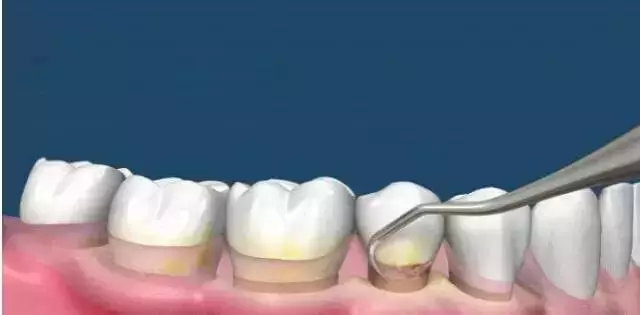

广大口腔专家说——其实刷牙只能清除牙齿表面和舌苔上的食物残渣,而牙线也只是清除牙间隙内的脏东西,但牙齿背面却一直是个死角位置,牙垢一旦钙化,牙齿背面将会成为牙周病的“第一案发现场”。那我们该怎么办呢?答案只有一个:洗牙!